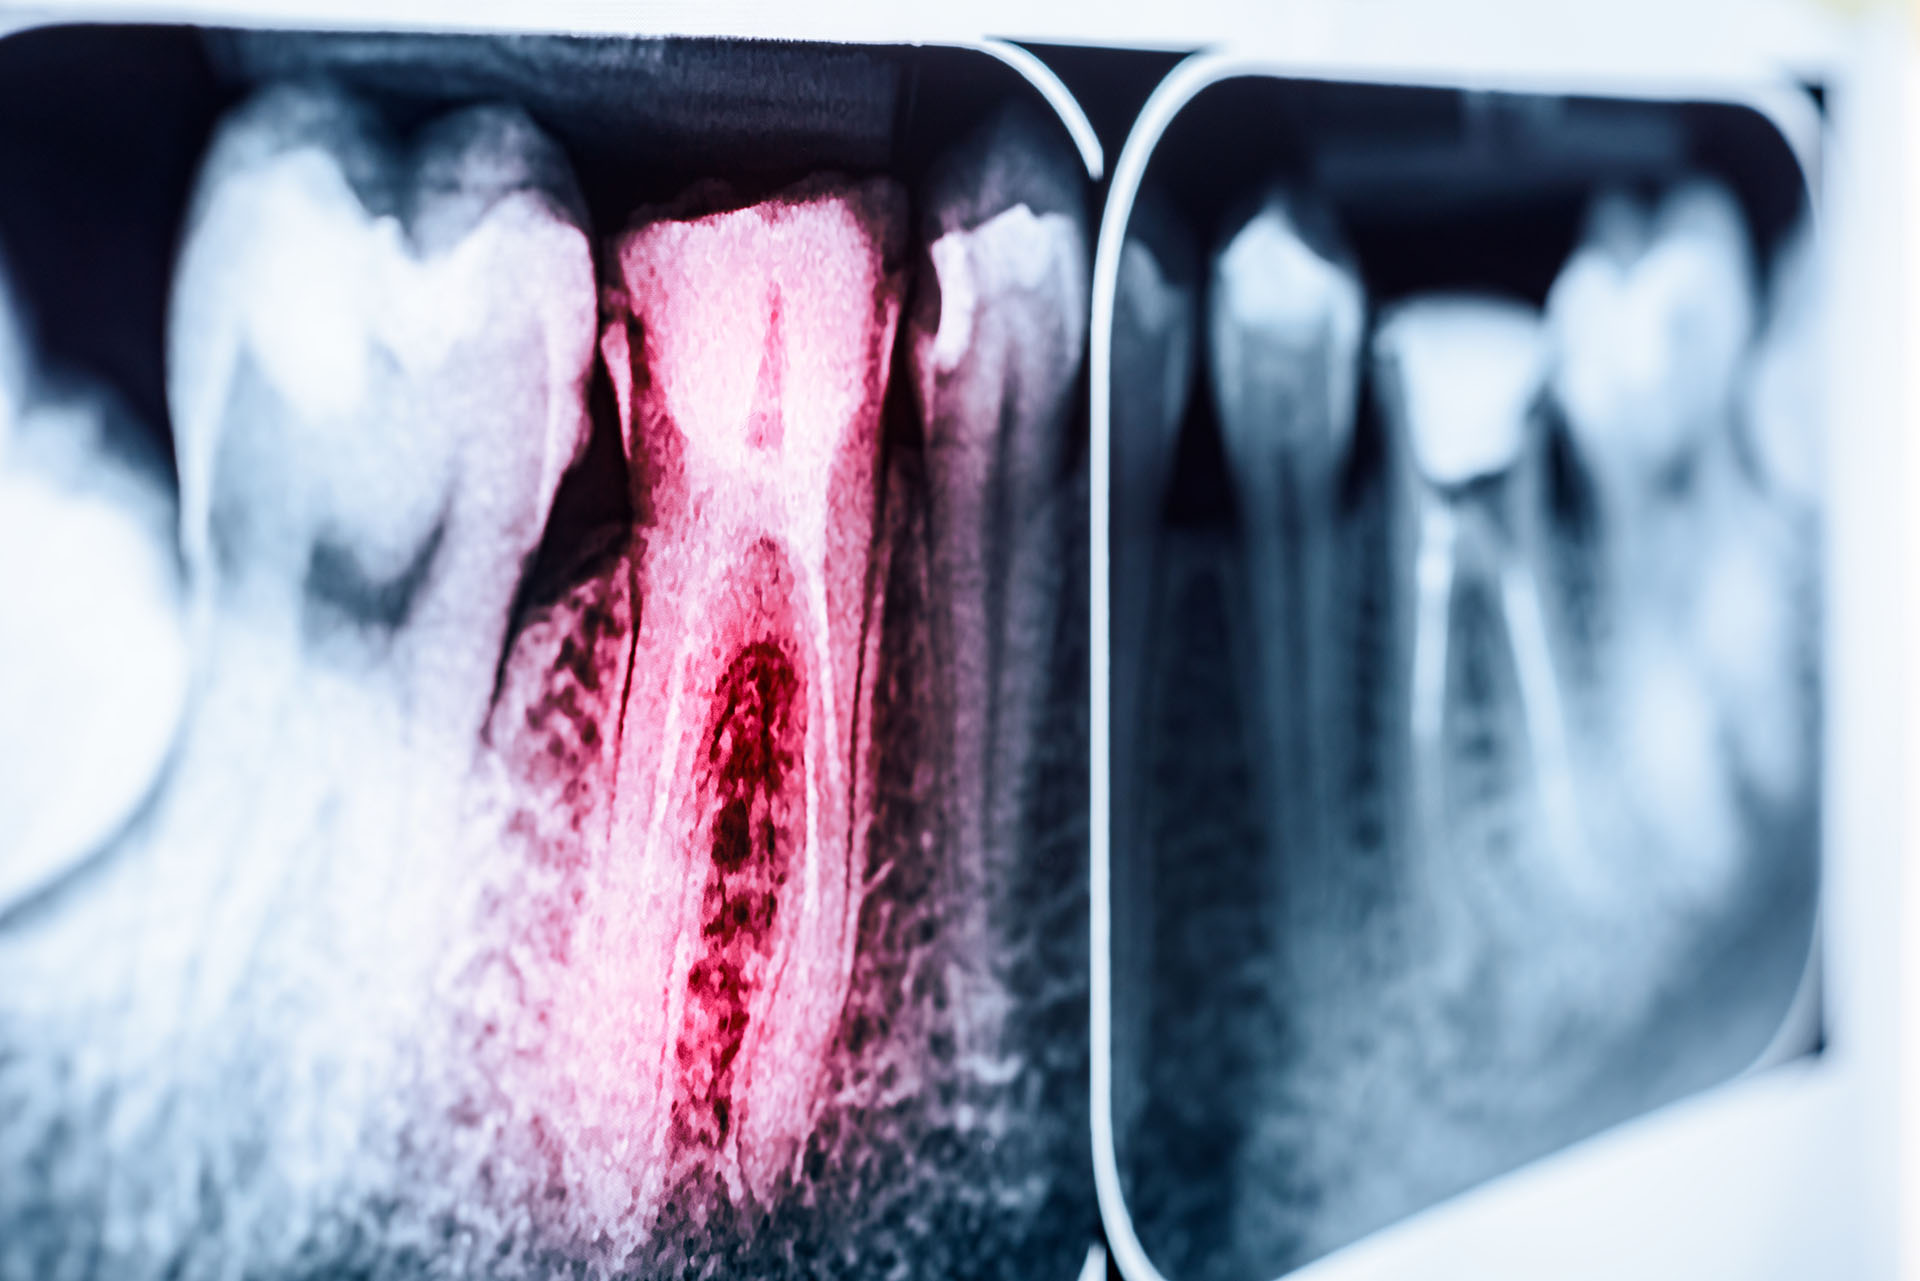

La competenza in questi casi rappresenta un valore di estrema importanza, in quanto l’odontoiatra deve applicare un protocollo specifico (linee guida dell’American Association of Endodontists) che prevede, oltre alle delicate fasi tecniche di ricostruzione, anche la programmazione di un iter di osservazione con controlli a distanza che permettono di monitorare la progressione nel tempo della terapia e di valutare precocemente eventuali ulteriori complicanze.

Anche a distanza di diversi anni dall’episodio traumatico possono infatti manifestarsi i segni di una disfunzione come:

– cambiamento del colore (il dente diventa rosa o grigio);

– perdita di vitalità (può essere asintomatica, può comparire una bollicina sulla gengiva in corrispondenza della radice del dente oppure può comparire gonfiore);

– anchilosi (il dente si “salda” all’osso, ma tu non puoi accorgertene, serve una visita dal dentista);

– reintrusione (il dente diventa più corto di quello a fianco).